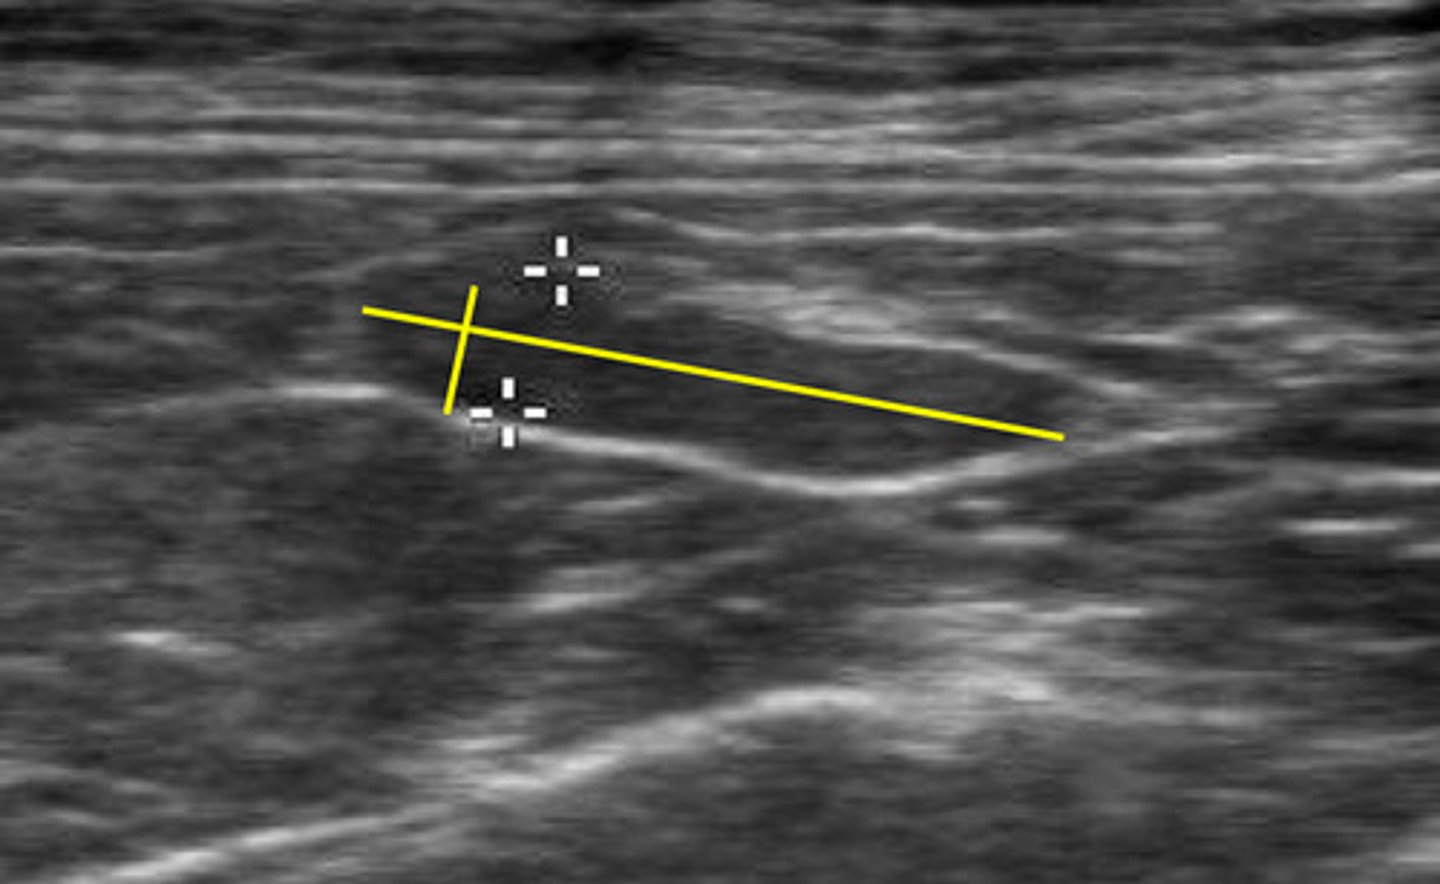

ID lymph node

medial iliac lns.

ID lymph node (hint: trifurcation near)

jejunal lns.